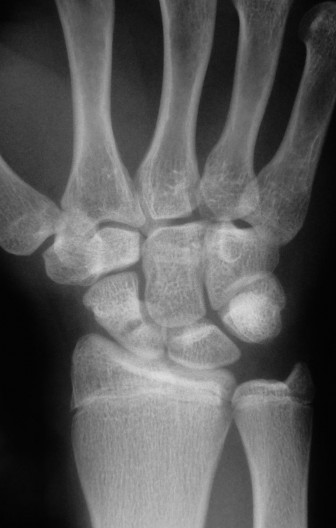

Plain radiography remains the initial screening tool. A dedicated scaphoid series must include posteroanterior (PA), true lateral, pronated oblique, and ulnar deviated (scaphoid) views. The ulnar deviated view extends the scaphoid, bringing its longitudinal axis parallel to the image receptor and unmasking subtle waist fractures.

However, plain films are notoriously inadequate for assessing fracture union or complex comminution. As demonstrated in the clinical scenario, when a patient returns at 8 weeks post-injury and the clinician must determine whether the fracture has definitively healed, a Computed Tomography (CT) scan is the gold standard. CT scans oriented along the longitudinal axis of the scaphoid provide unparalleled visualization of trabecular bridging. A fracture is generally considered healed when greater than 50% trabecular bridging is observed across the fracture site.